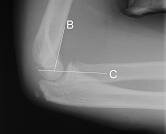

Radiology Challenge: "I can't move my elbow!"

Gelareh Zargaraff, MD, Michael I. Zucker, MD